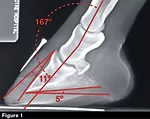

Shoeing Principles for Club Feet

For veterinarians and farriers to properly address club feet, early intervention is the key

With his work in Kentucky, Craig Lesser finds management of club feet to be a common issue. Practicing out of Rood & Riddle Equine Hospital in Lexington, Ky., the equine veterinarian and American Farrier’s Association certified farrier approaches these cases from that dual perspective.